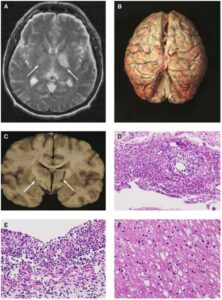

La meningite è una malattia infiammatoria mortale che colpisce le membrane del cervello.

Tra i maggiori responsabili c’è il pneumococco, un batterio che provoca circa il 50% dei casi di meningite umana. E «la meningite si sviluppa quando questi batteri riescono a penetrare la barriera emato-encefalica» ha dichiarato il professor Victor Nizet, della divisione di pediatria e farmacia presso la School of Medicine and Skaggs School of Pharmacy and Pharmaceutical Sciences (UCSD).

La “barriera” è solitamente un mezzo efficace per tenere lontani agenti patogeni che potrebbero attaccare il cervello e mantenere un ambiente biochimico ottimale per il funzionamento del cervello. Però, in questo caso, si è scoperto che questa proteina chiamata “Nana” riesce a far superare questa barriera ai batteri e a permettere il loro ingresso nel sistema nervoso centrale.